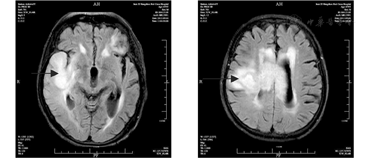

麻痹性痴呆患者头颅磁共振(MRI)检查,提示有右颞叶、右侧脑室旁及双顶叶高信号,呈占位性病变。

注:(a)右颞叶异常高信号(箭头所示);(b)右侧脑室旁异常高信号(箭头所示)